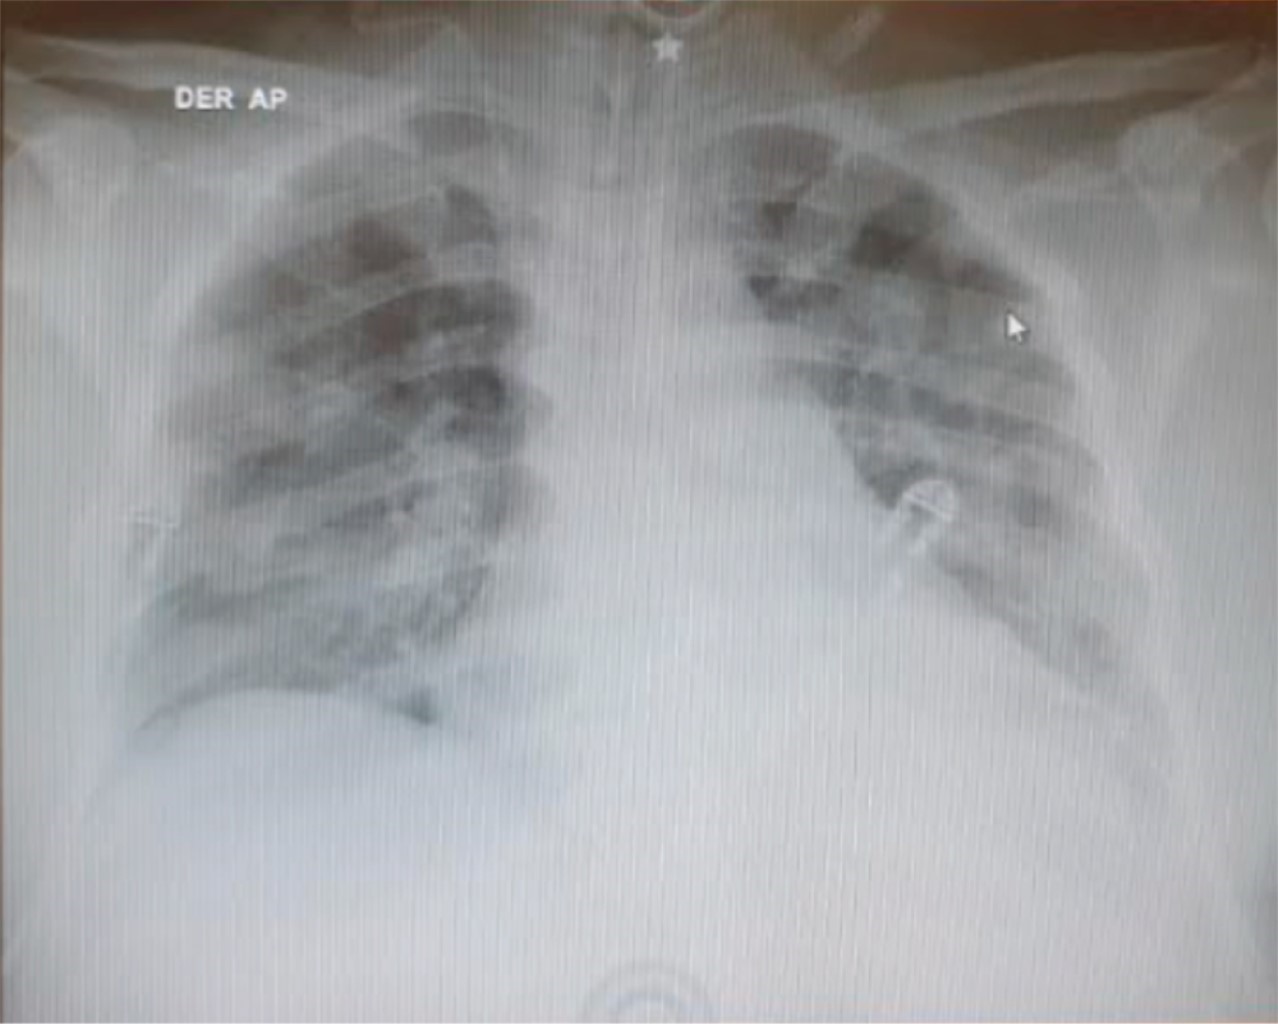

Durante su estancia hospitalaria y 24 horas antes del procedimiento quirúrgico, cursa con un cuadro de odinofagia, tos sin presencia de disnea y fiebre de 39 grados, la cual cede a la administración de antipiréticos orales. Ingresó a quirófano, para craneotomía minipterional izquierda y clipaje de aneurisma, sin embargo, durante el procedimiento, se reportan alteraciones en la mecánica respiratoria, y una alta demanda de soporte ventilatorio (incremento en valores de PEEP). Ingresa a la Unidad de Cuidados Intensivos bajo sedación, orointubado, con PaO2/FiO2 menor a 150. La radiografía de tórax muestra un patrón con infiltrados bilaterales en vidrio esmerilado, y durante las siguientes horas se registra fiebre de 38o grados (Figura 1). Se realiza prueba de reacción en cadena de la polimerasa (PCR) para SARS-CoV-2 por raspado nasofaríngeo, cuyo resultado fue positivo. Se inicia tratamiento con azitromicina, vitamina C, metilprednisolona e inmunoglobulina intravenosa.

Figura 1